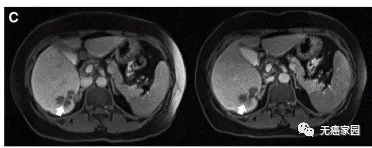

通过MRI观察到患者P10的一个肝脏病变发生萎缩